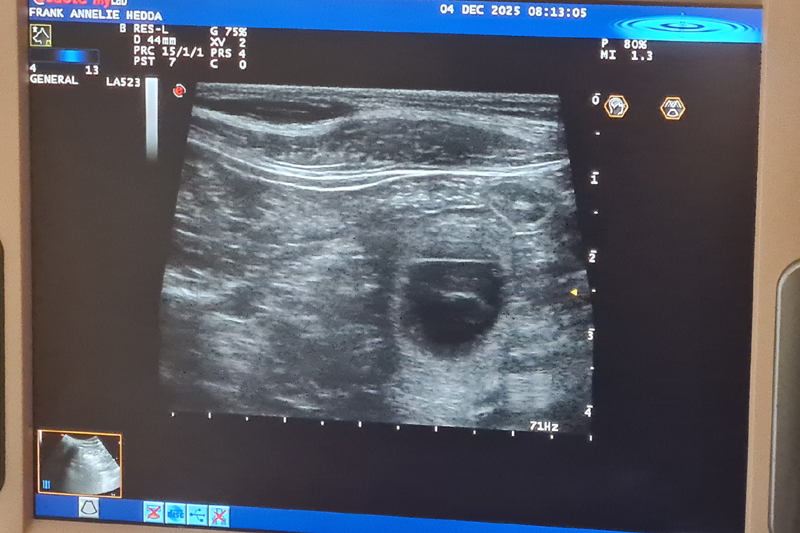

Lotta är dräktig!!

Vi har gjort ultraljud och det finns många valpar i Lottas mage!! Stolt pappa är Bertil (Actualis Winter Surprise).

Valparna föds i mitten av januari och vill flytta till sina nya familjer i matten av mars.